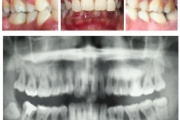

GAgP 25 aastasel suitsetaval puuduliku suuhügieeniga patsiendil